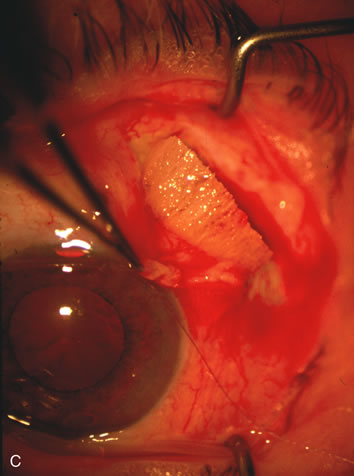

In years past, patients with both cataract and glaucoma frequently provided overwhelming surgical challenges for the ophthalmologist. The ability to carry out phacoemulsification through a 3.2-mm corneal incision along with inserting a foldable IOL is a vast improvement over 11-mm incisions that were common a decade ago (Fig. 1). The anatomical and inflammatory changes to the eye are less with small incision techniques, improving the likelihood of success with concomitant glaucoma surgery. Pharmacologic inhibition of fibrosis along with postoperative wound revision increases the long-term success rate of filtration surgery when combined with lens extraction. (Fig. 2). The learning curve may be steep at times, but the blending of cataract and glaucoma surgical skills slowly falls into place as the surgeon constantly learns and upgrades his or her technique.

Fig. 1. The anatomic advantage of small incision cataract surgery for the glaucoma patient. A. Long-term bleb function with a large cataract incision is difficult to achieve with either ECCE-trabeculectomy or trabeculectomy followed later by ECCE. This bleb failed to form sufficiently when combined with large incision ECCE. The inflammation, bleeding, and long-term wound healing with stimulation of fibroblasts associated with this technique are more likely to cause bleb failure. In addition, the increased iris manipulation necessary to deliver the nucleus and subsequent iris repair adds to the long-term breakdown of the blood aqueous barrier. B and C. Two-site phacotrabeculectomy has the advantage of small incision cataract surgery combined with separate site trabeculectomy. The incision size is one third the size of the standard ECCE. The inflammation is less severe, and cataract wound healing is confined to the temporal area. Visual rehabilitation with phacoemulsification and foldable IOL is much faster. Phacoemulsification allows successful lens extraction even in the unfriendly environment of a smaller pupil compared with ECCE. The trabeculectomy is performed in an entirely different site, well away from the wound healing associated with temporal phacoemulsification. The likelihood of this filter functioning long-term is greater than with ECCE-trabeculectomy. D. The surgeon also has the option of single-site phacotrabeculectomy with foldable IOL. Both the lens extraction and trabeculectomy are performed through one small 3.5-mm limbal incision.